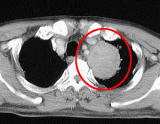

放射線治療によりがんが小さくなった例